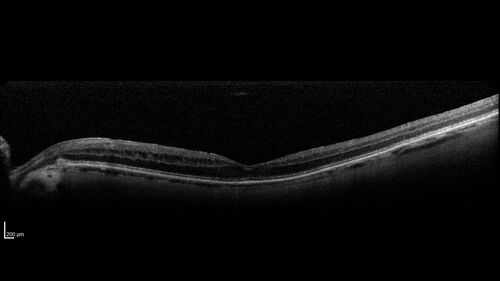

Paclitaxel induced cystoid macular edema - reversed when chemo stopped

74 year old retired physician  About 2-3 weeks ago there was gradual vision loss in the right eye. The patient was seen by an ophthalmologist who saw macular swelling and injected vabysmo. He has been on chemotherapy (Carbiplatin and Carboxytaxol for 2 cancers - advanced prostrate diagnosed 2019 - has had brain surgery AND squamous lung cancers treated with radiation)

Medical Hx: Prostate cancer (Onset: 2018). Pulmonary and bone cancer metastatic. Brain cancer metastasized from prostate cancer.

Surgical Hx: Right frontal & Frontoparietal Craniotomy (Onset: 2024). Appendectomy. Hemorrhoidectomy. Herniorrhaphy. Prostate. Systemic Meds: Chemotherapy. Radiation. Eligard Every 3 Months 22.5 MG per 0.375 ML Prefilled Syringe. MIRALAX prn. Tums Freshers 500 MG Chewable Tablet. Vitamin D. XGEVA.

VA OD: Dcc20/125+1

VA OS: Dcc20/125-2

TP: OD:12 OS:15